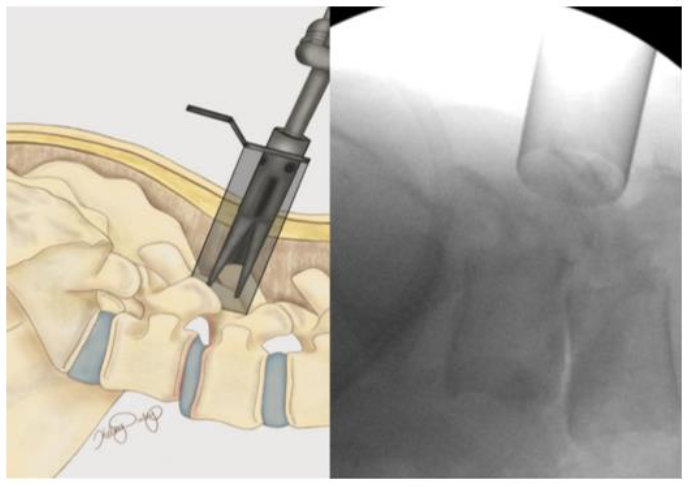

The patient is positioned prone on a spinal Jackson table, the area of interest is prepped and draped in a sterile fashion. The index level is localized utilizing lateral fluoroscopy. An incision is then made 3 cm lateral to the midline overlying the appropriate disc space. The fascia is incised parallel to the spinous processes and the One-Step-Dilator (BoneBac/Thompson MIS, Sandown, NH) is used to approach the spine in a muscle sparing fashion (Figure 3). The dilator is supported by a holder and once docked on the facet, counter clock-wise rotation opens the flanges of the dilator, separating the muscle tissue. A tubular retractor of the appropriate length is then placed over the one step dilator and the dilator is removed. The tubular retractor is attached to a support arm (Walter Arm, Zimmer Spine) which has been fastened to the operative table.

Figure 3. One-step dilator (Thompson MIS/Bonebac, Sandown, NH) placement